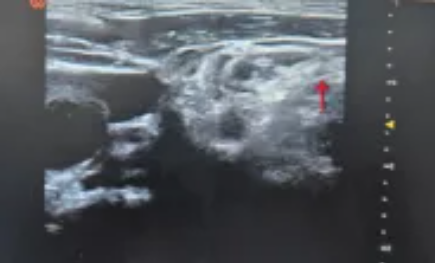

图为超声引导下C6神经根阻滞

红色箭头处为穿刺针显影(治疗神经根型颈椎病)